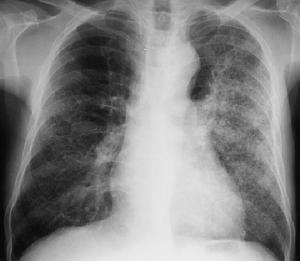

發病前不少患者有呼吸道感染,以後有反覆咯血,大多數出現在腎臟病變之前。X線檢查見兩肺有瀰漫性或結節狀陰影,自肺門向周圍擴散,肺尖及近膈肌處清晰,常一側較重,有的無咯血史,但經痰含鐵血黃素及胸片檢查證實有出血。在咯血時肺彌散功能減退,出現低氧血症,貧血常見。

肺出血發病前不少患者有呼吸道感染以後有反覆咯血大多數出現在腎臟病變之前長者數年(最長可達12年)短者數月少數則在腎炎後發生X線檢查見兩肺有瀰漫性或結節狀陰影自肺門向周圍擴散肺尖及近膈肌處清晰常一側較重有的無咯血史但經痰含鐵血黃素及胸片檢查證實有出血在咯血時肺彌散功能減退出現低氧血症貧血常見